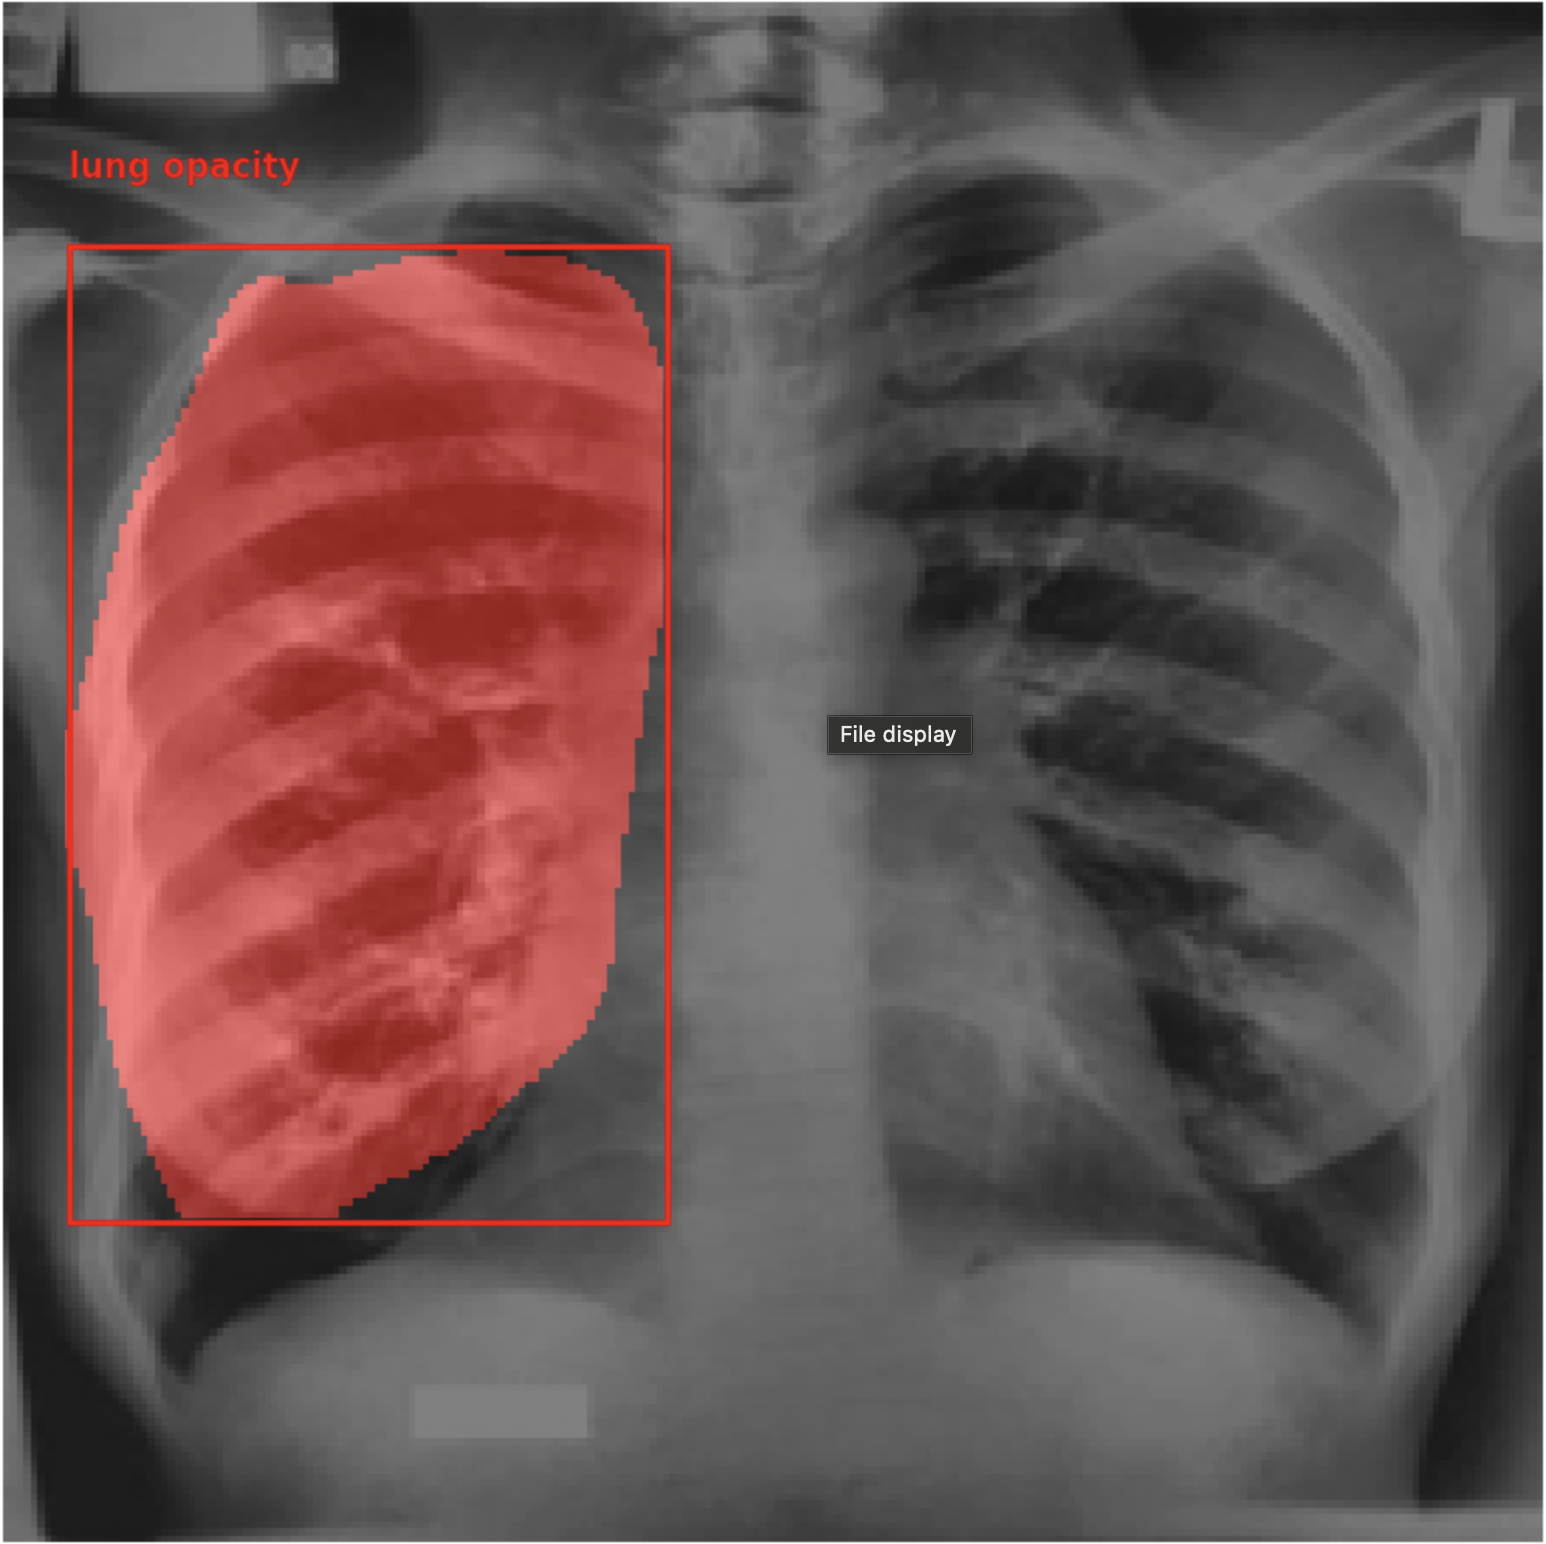

Figure 4 shows the bounding boxes predicted by PaliGemma-CXR. PaliGemma detects the pathologies in the image. It can detect multiple instances of the same pathology as well as different pathologies occurring within the same image.

Refer to caption

(a)

(b)

(c)

(d)

Figure 4: (a) shows the bounding boxes predicted by PaliGemma-CXR and (b) shows the ground truth bounding boxes, (c) shows the ground truth segmentation mask and (d) shows the segmentation mask generated by PaliGemma-CXR.

Figure 4, shows the segmentation masks predicted by PaliGemma-CXR. It successfully segments predicts segmentation masks with a high IoU with the ground truth segmentation mask.